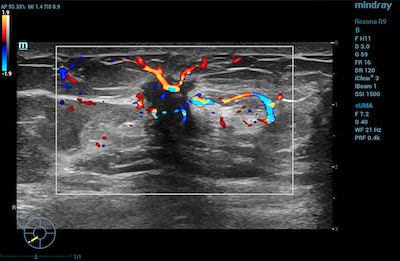

- Musculoskeletal – CDI may be used to visualize rheumatological changes in diseased joints and can provide diagnostic information for assessing damage to tendons and ligaments.

Color Doppler Imaging of Musculoskeletal Lesion